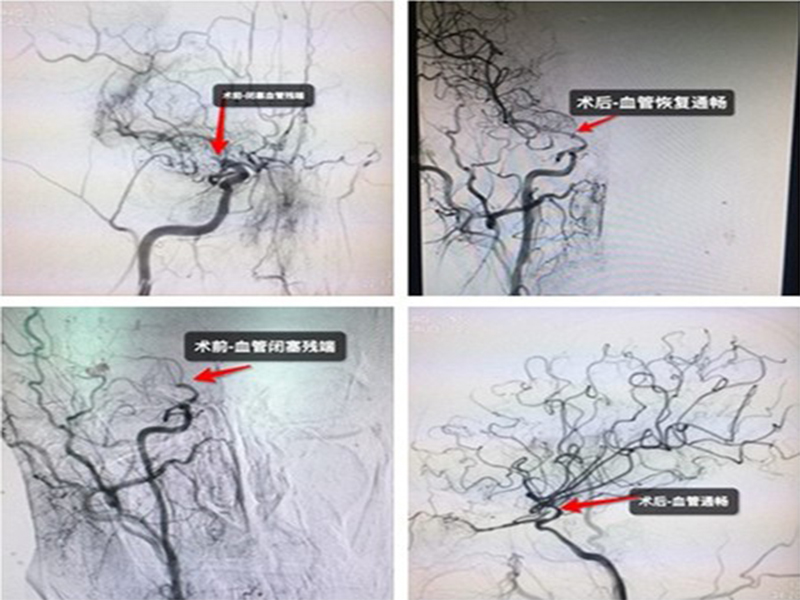

54 《 CT 1 4 M1 1 5 M1 24 CT